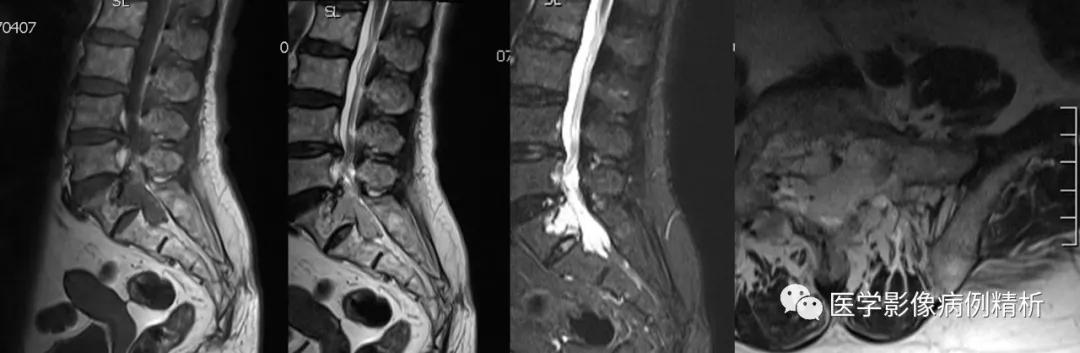

MRI平扫对比图

MRI增强对比图

如图所示,红色箭头可见不规则形异常信号,轴位呈哑铃型,病灶前缘侵及骶1、2椎体后缘,绿色箭头见骨质局部破坏,病灶T1低信号,T2稍高信号,压脂像明显高信号,信号尚均匀,腰4-5、腰5骶1椎间盘向后方突出,硬膜囊受压,蓝色箭头可见腰4-5椎间盘后缘纤维化小点状T2高信号,提示纤维环后缘撕裂。本例骶1-2椎间盘形成,骶1椎体腰化不完全。

如图所示,分别为T1WI增强矢状位、冠状位、轴位,T1WI增强矢状位与T2WI压脂像非常相像,注意椎管内脑脊液信号,T1WI增强为低信号与T2WI压脂像高信号正好相反。红色箭头所示病灶明显强化,呈亮灯征感觉,清晰显示病灶范围,绿色箭头所示为病灶侵及骶1椎体后缘形成不规则形骨质破坏区。

红色箭头:病灶位于骶1-2椎体水平,轴位呈哑铃型,CT见骶1-2椎体后缘受侵、骨质破坏;MRI见病灶主体沿骶管及双侧骶孔生长,以左侧骶孔为著,T1低信号,T2稍高信号,压脂像高信号,接近脑脊液信号。

绿色箭头:骶1-2椎体后缘见信号向内部侵犯,边缘毛糙。

描述:腰椎生理曲度存在,序列规整。所见椎体骨质边缘变尖、T1WI及T2WI均呈不均高信号,压脂像均匀低信号。腰4-5、腰5骶1椎间盘向后方突出,硬膜囊受压。骶1-2椎体水平骶管及双侧骶孔扩大,内见哑铃型异常信号,大小约6cmx5cmx3.5cm,T1WI低信号,T2WI稍高信号,压脂像高信号,病灶侵及骶1-2椎体后缘骨质,增强明显强化。